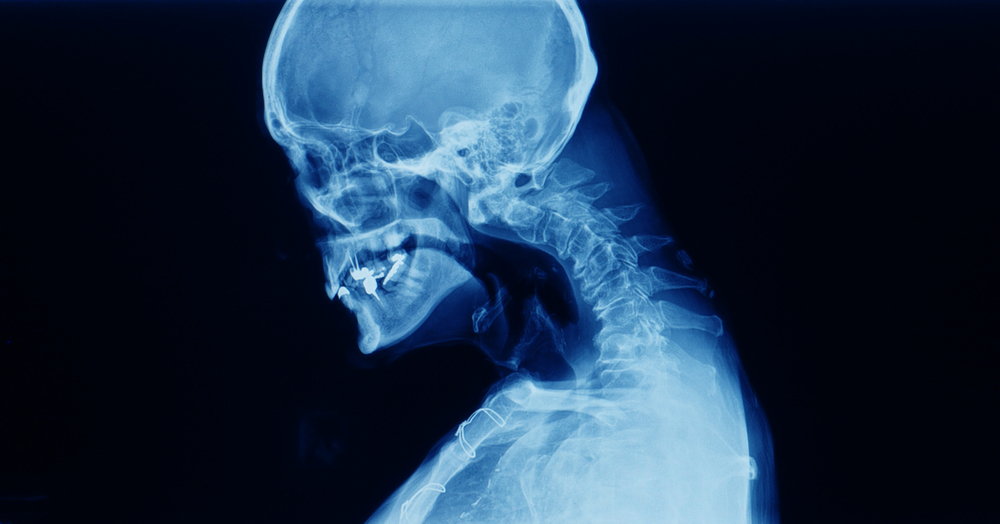

Egy iráni fiatalembert láttak, akinél riasztó állapot alakult ki. A nyaka már nem tudta megtartani a fejét. Az orvosok szerint a férfi amfetaminhasználó volt. A speedként is ismert anyag hatására az álla hosszabb időre a mellkasára esett, ami „rögzített kyphotikus nyakpozíciót” váltott ki.

A férfi nyakán extrém görbület alakult ki, miután rendszeresen számtalan kábítószert fogyasztott, amelyek között többek között heroin, ópium és speed is szerepelt.

Dr. Majid Rezvan, az esettanulmány társszerzője elmondta: „Felfedeztük, hogy a kábítószerrel való visszaélés hozzájárult a súlyos, komplikált nyaki kyphosis [a hát felső részének túlzott gömbölyűsége] szokatlan kialakulásához”.

„Ehelyett van egy közvetett hatás: amikor a beteg a kábítószert használja, hosszú ideig egy bizonyos pozícióban marad, és ez hónapok alatt olyan mozgásszervi változásokat eredményez, amelyek kyphoscolizishoz vezettek” – magyarázta.

A leesett fej szindrómát lógó fej szindrómának is nevezik, és néha gyenge nyakizmokkal rendelkező embereknél fordul elő.

A CT-vizsgálat kimutatta, hogy a gerince súlyosan deformálódott. Az orvosok szerint a dolgok javulni látszottak, amikor általános érzéstelenítésben volt.